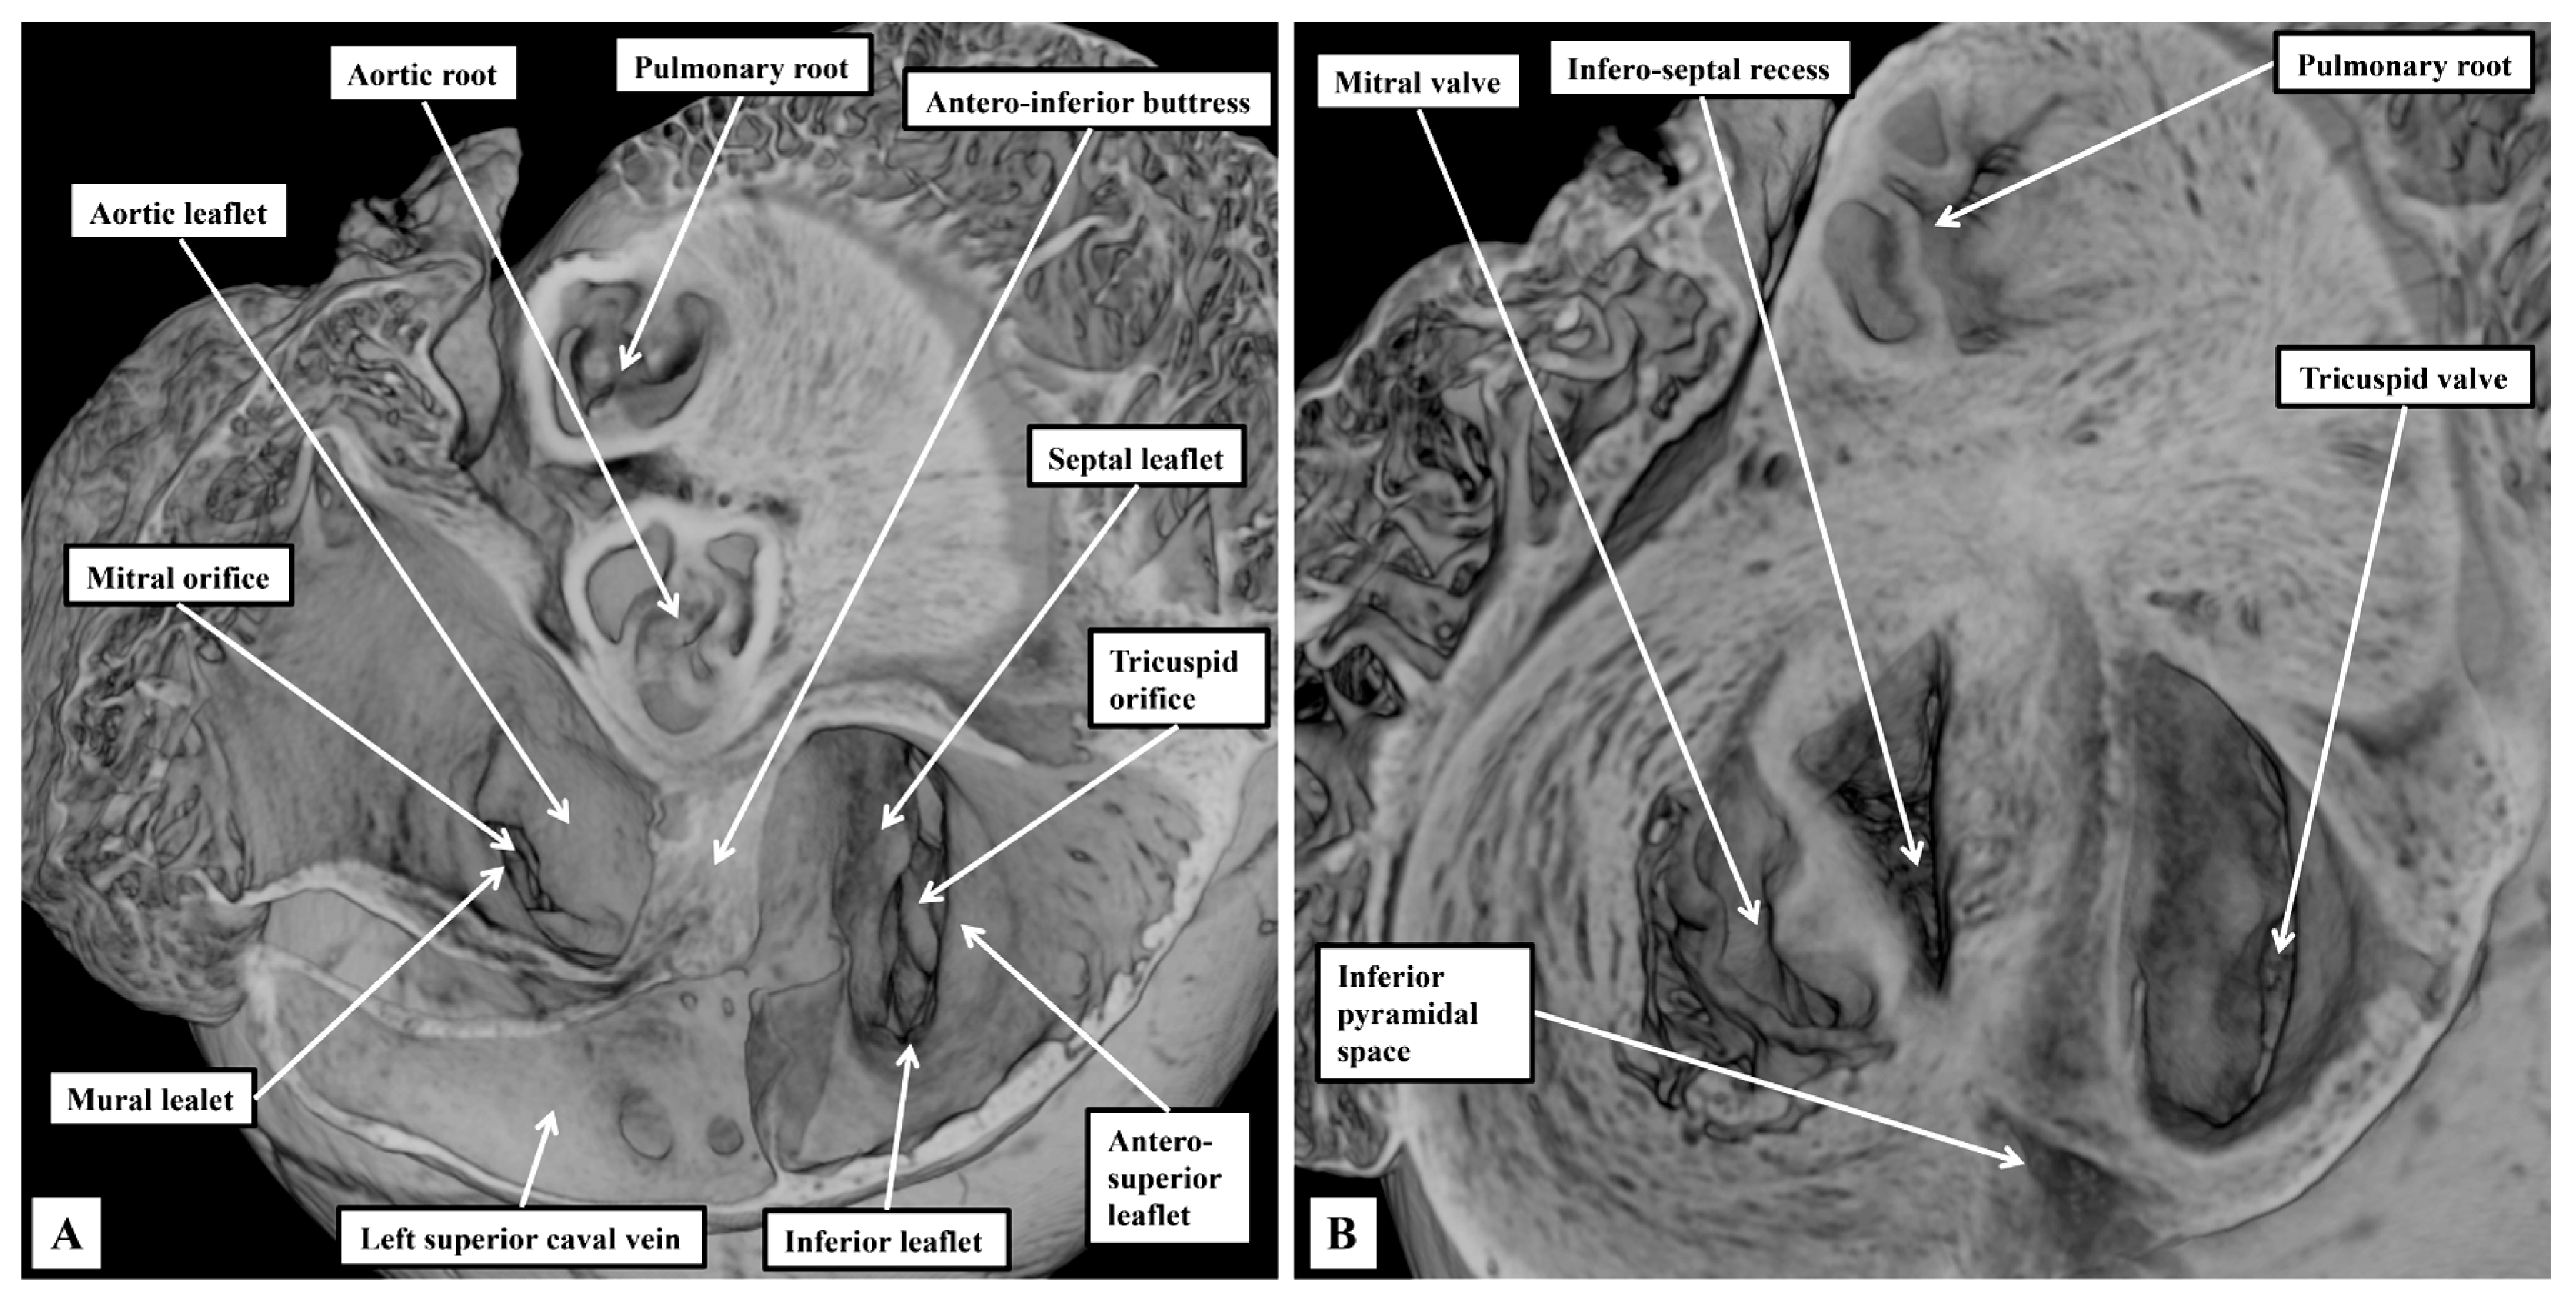

3.1. Gross Anatomy

3.2. The Arrangement of the Conduction Tissues